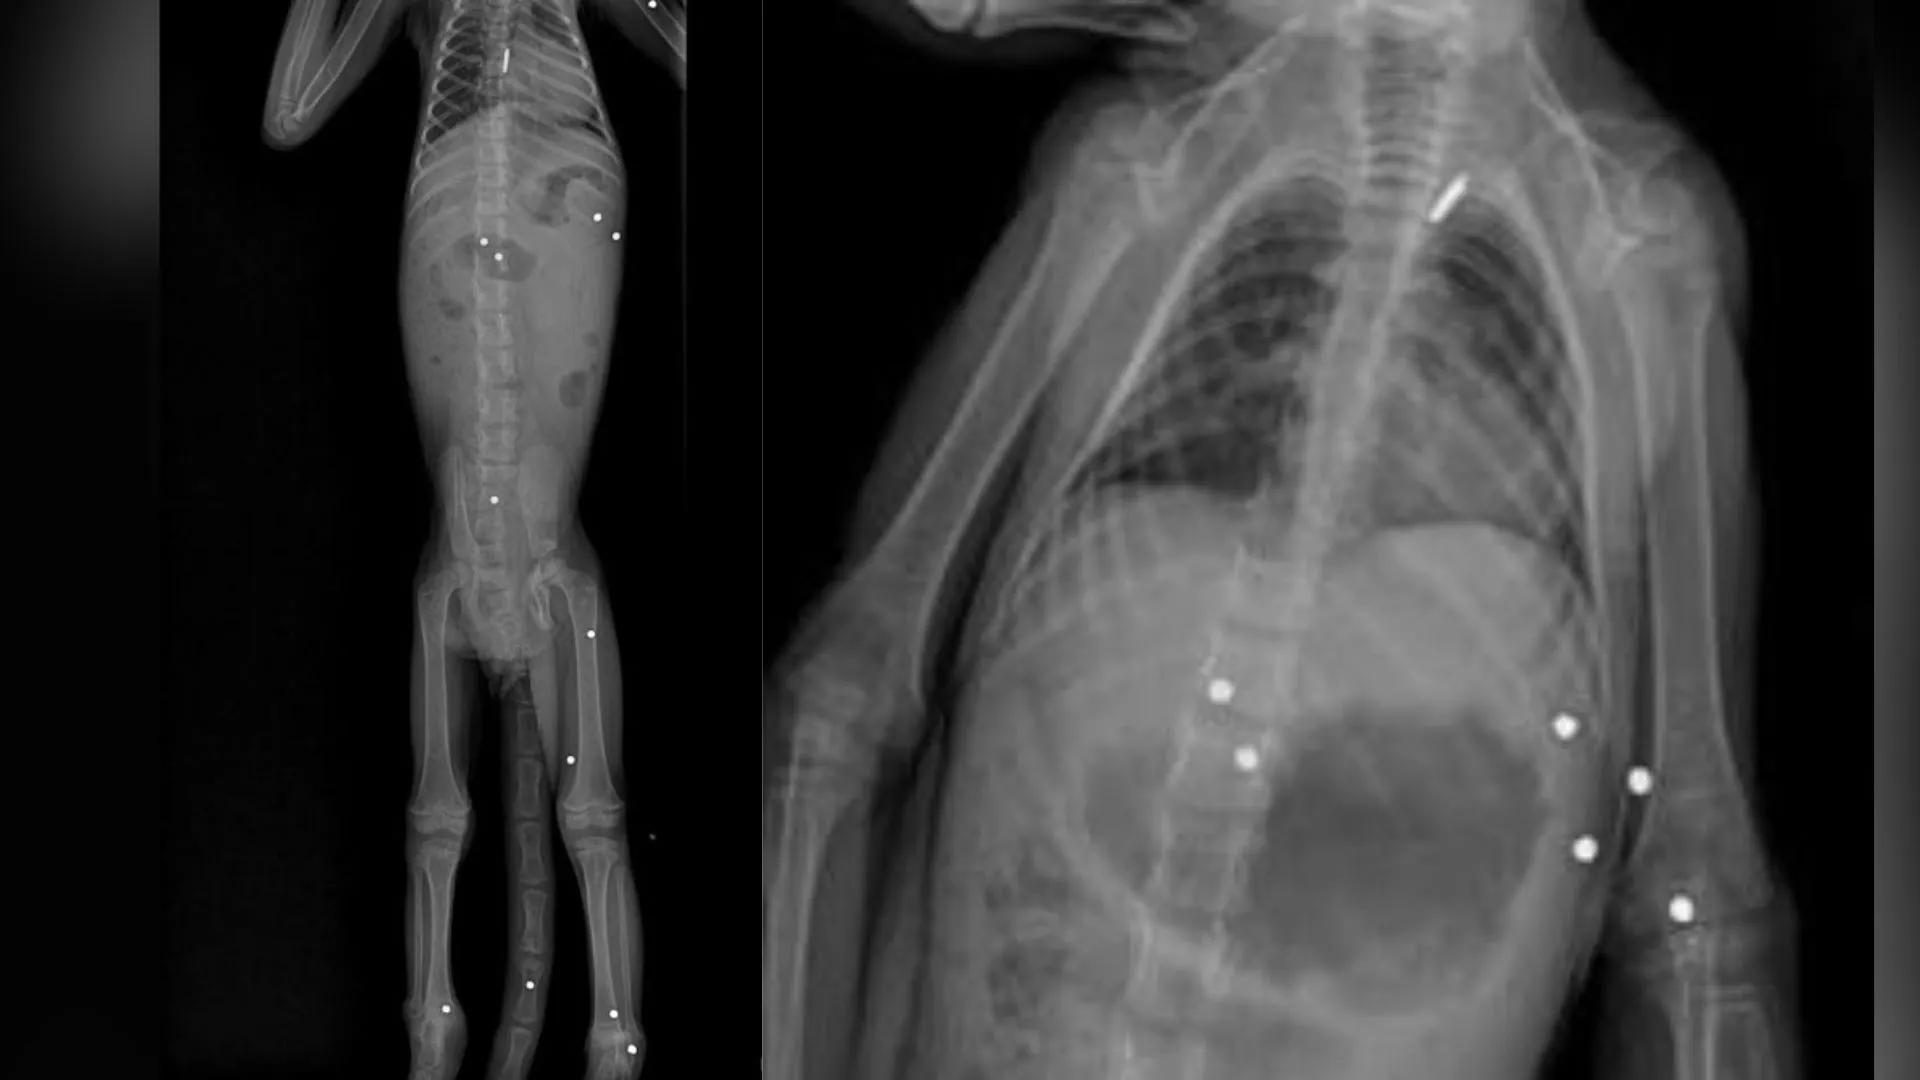

Durante la evaluación, los especialistas identificaron múltiples afectaciones en el sistema osteomuscular del mono, las cuales comprometían seriamente su estado de salud. Según explicó el médico veterinario Andrés Rodríguez, los estudios radiográficos fueron clave para establecer el origen del deterioro.

“Al realizar las ayudas diagnósticas pertinentes, particularmente el examen radiográfico, se evidenció la presencia de 19 perdigones alojados en el cuerpo del individuo”, indicó el profesional.

De acuerdo con el informe médico, los proyectiles —de aproximadamente 3 milímetros de diámetro— se encontraban distribuidos en diferentes partes del cuerpo, generando un impacto directo en la movilidad del animal, especialmente en una de sus extremidades. Estas lesiones provocaron un deterioro progresivo que finalmente derivó en su muerte.